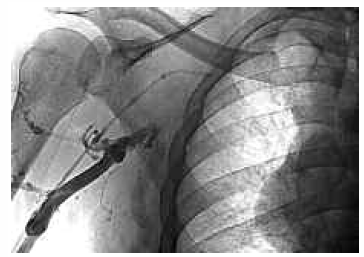

At CABG, there was a large aneurysm of the aortic root. A left internal mammary artery graft to the left anterior descending coronary artery was performed off pump. Two 4-0 Prolene purse-string sutures were inserted into the right atrial appendage before inserting each Tesio line. The purse-string sutures were secured individually, with progressive invagination of the surrounding atrial appendage tissue. The lines were tunneled following the pleural-pericardial reflection, with an exit site in the upper abdominal wall just below the costal margin (Figure 2). Correct positioning was confirmed at the time of insertion using image intensification.

Figure 2. Intra-atrial dialysis line inserted during CABG.